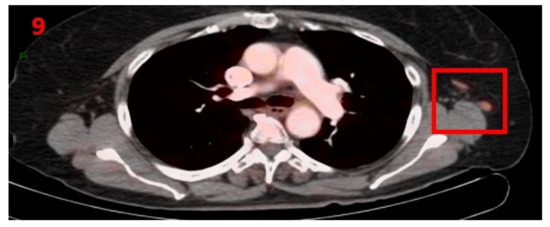

3.9. Case No 9

| Case no.9 | Follicular lymphoma | Left arm | 12 days | Hypermetabolic uptake in the left axillary region and lymphadenopathy | Second vaccine | 7 mm | 1.9 | Pfizer-BioNTech |